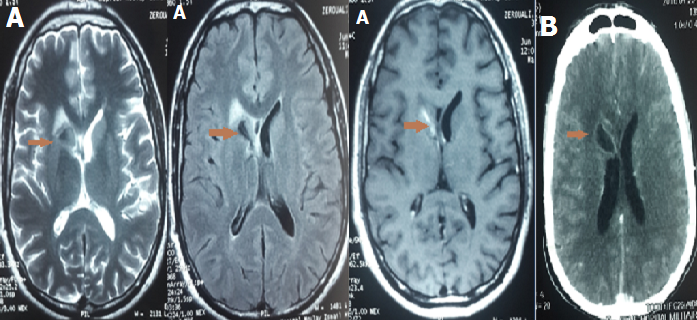

Nous rapportons l’observation d’un patient de 30 ans qui a présenté un syndrome méningé fébrile. L’examen du LCR retrouvait une méningite lymphocytaire à 400 éléments blancs avec hypoglucorachie évoquant une méningite tuberculeuse. Une imagerie cérébrale (TDM puis IRM) (A, B) a été réalisée. Elle révéla la présence d’un tuberculome cérébral localisé au niveau du noyau caudé. Le patient a été mis sous traitement anti-bacillaire avec bonne évolution. Les tuberculomes constituent une complication rare des atteintes tuberculeuses du SNC. Leur siège de prédilection est la jonction substance blanche-grise. Leur diagnostic repose sur l’imagerie. Ils peuvent être uniques ou multiples. Au scanner, ils se traduisent par une image arrondie ou ovalaire hypodense ou isodense, avec rehaussement rapide après injection du produit de contraste. Il peut exister un renforcement périphérique en anneau réalisant l’aspect classique en cocarde. En imagerie par résonnance magnétique, les tuberculomes et l’œdème périlésionnel sont hypointenses au parenchyme cérébral en séquence T1. L’injection de gadolinium retrouve l’aspect de rehaussement annulaire classique en TDM. En T2, ils se traduisent par un signal hypo-intense avec plusieurs hypersignaux punctiformes à l’intérieur de la lésion et une zone pérphérique irrégulière d’hypersignal correspondant à l’œdème. L’IRM est l’examen de choix pour le diagnostic des tuberculomes cérébraux. Elle permet surtout par rapport à la TDM d’apprécier l’extension et les différentes composantes de la lésion (centre nécrotique, capsule et œdème péri-lésionnel).